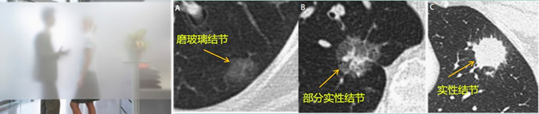

TOP5、CT报告为何要区分磨玻璃结节、混合磨玻璃结节、实性结节?

张伟:根据CT密度的不同,肺结节可以分成三类:磨玻璃结节、混合磨玻璃结节、实性结节(如图)。由于三类结节疾病谱、诊断、随访时间均有所差别,所以CT报告需要加以区分。